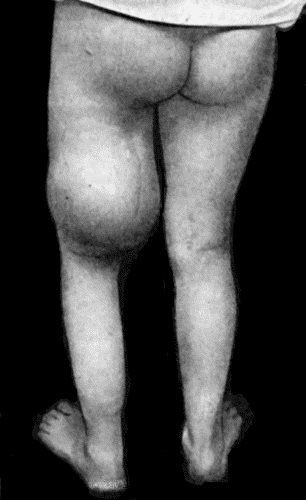

Acute Bed Sores over right Buttock

474 135.Cadaver, illustrating the alterations in the Lower Limbs resulting from Ostitis Deformans

475 136.Osteomyelitis Fibrosa affecting Femora